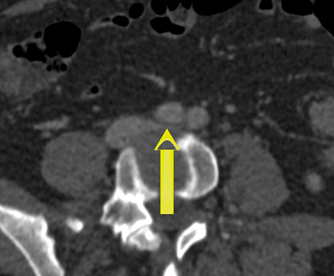

Venografía por CT de estenosis crítica de la vena ilíaca común izquierda (síndrome de May-Thurner).